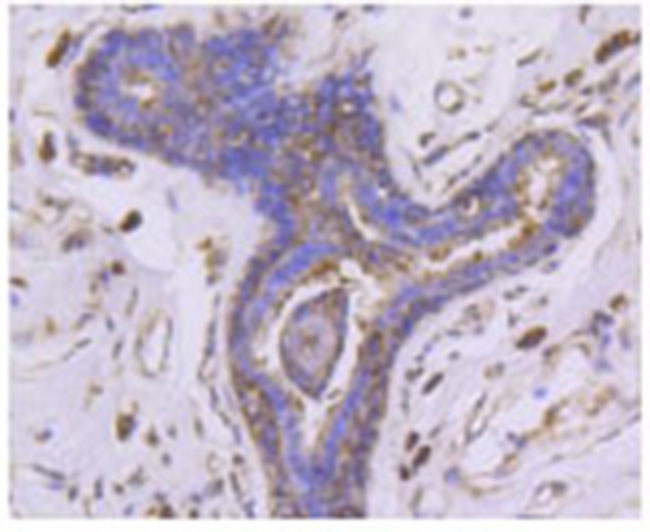

| Fig. 1. Western blot analysis of PHD1 on different lysates using anti-PHD1 antibody at 1/1,000 dilution. Positive control: Lane 1: Hela; Lane 2: PC12; Lane 3: NIH/3T3 | Fig. 2. Immunohistochemical analysis of paraffin-embedded human breast carcinoma tissue using anti-PHD1 antibody.Counter stained with hematoxylin. |